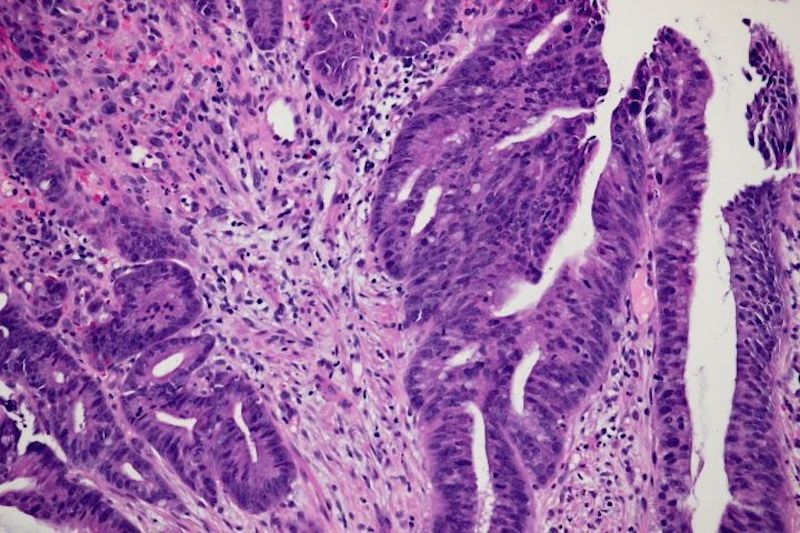

Dr. Shihabi received his anatomic and clinical pathology training at UCSF, completing his surgical pathology fellowship at UCSF with an intense focus on gastrointestinal pathology. Dr. Shihabi is board-certified in Clinical and Anatomic Pathology. At CoCoPath, we offer a breadth of expertise and experience in the diagnosis of various gastrointestinal disorders, including: